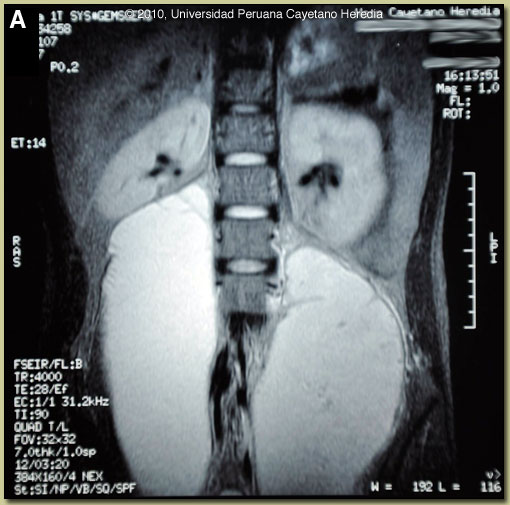

| Diagnosis: Pott’s Disease (TB spondylitis) with giant paravertebral abscesses due to Mycobacterium tuberculosis. |

Discussion: Ultrasound guided percutaneous drainage of both paravertebral collections yielded 600 cc from the right and 700 cc from the left collection. Gram stain and bacterial culture was negative, AFB stain was positive, mycobacterial culture results are pending. The MRI was not performed with windows appropriate for bone. A CT scan of the spine showed lytic lesions and disk-space narrowing at L4-5 and L5-S1 levels; no new bone formation was observed [Image B]. Sputum AFB was negative at time of this presentation. Further history indicated that 1-month prior to the onset of lumbar pain the patient had presented dry cough, low grade fever and weight loss and was diagnosed with pulmonary TB based on a 2+ positive AFB stain of sputum sample. He had been started on the standard 4-drug initiation regimen of daily INH, rifampin, ethambutol, and pyrazinamide.